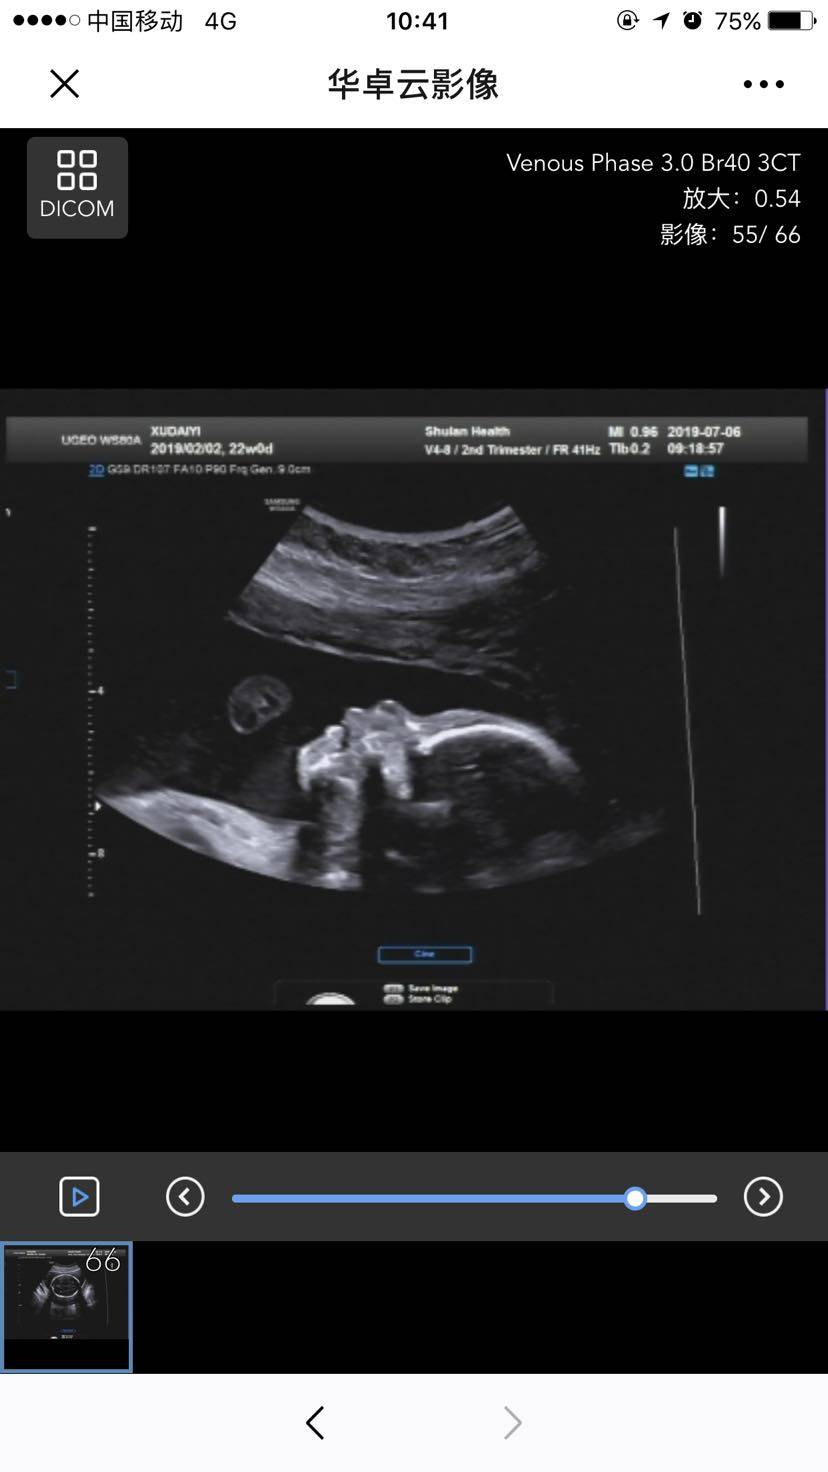

今天四维彩超和胎儿心脏超声顺利通过😁

今天宝宝22周了,12+6做NT的时候就预约了今天的四维和胎心超声,一切正常,悬着的心放下了,因为我抗核抗体ssa阳性、ssb弱阳,所以有点担心,现在可以安心了,做四维的时候医生说,看来你要爬半个小时楼梯了,今天做了三个都要爬,然后让我半侧躺,没想到一下子全部做好了,那心情跟坐过山车一样,出来的时候外面等着的人羡慕我做的快😄还好我宝宝乖,NT一次性过,糖筛也一次性过,四维也一次性过,胎儿心脏超声也一次性过,接下去就等24周以后的糖耐了,估计也会一次性过✌️